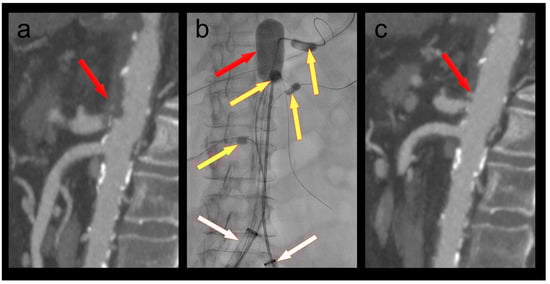

3.6. Patient 6

A 68-year-old female patient was admitted to the emergency department with chest pain as well as rest pain in both legs. She was diagnosed with acute ischemia of both legs and an inferior ST-elevation myocardial infarction. CT angiography revealed an occlusion of her distal aorta. After stent PCI of her right coronary artery, she was transferred to the hybrid operating room, where her aorta was thrombectomized with her hypogastric arteries protected by 4F OTW Fogarty® catheters (Figure 3). When passing the thrombectomy balloon through the underlying stenosis in the distal aorta, a rupture of the latter occurred. This was treated by a covered endovascular reconstruction of the aortic bifurcation (CERAB) using Gore® Viabahn® VBX balloon expandable stentgrafts (W. L. Gore & Associates, Inc., Flagstaff, AZ, USA). Furthermore, a near occlusion of her left renal artery was stented, and a near occlusion of her right accessory renal artery was dilated. The patient recovered both from her myocardial infarction and her limb ischemia. She was discharged to cardiac rehabilitation with bilaterally palpable foot pulses.

Figure 3. (a) Occlusion of the infrarenal aorta (red arrow); (b) thrombectomy of the infrarenal aorta (red arrow) under balloon protection of both hypogastric arteries (yellow arrows). The large-bore sheaths are occlusive in both external iliac arteries (white arrows); (c) iatrogenic rupture of the infrarenal aorta; (d) covered endovascular reconstruction of the aortic bifurcation (red arrows); (e) stenoses at the origins of the left renal and a right accessory renal artery (red arrows); (f) no residual stenoses after PTA of the right accessory renal and PTA/stenting of the left renal artery (red arrows).